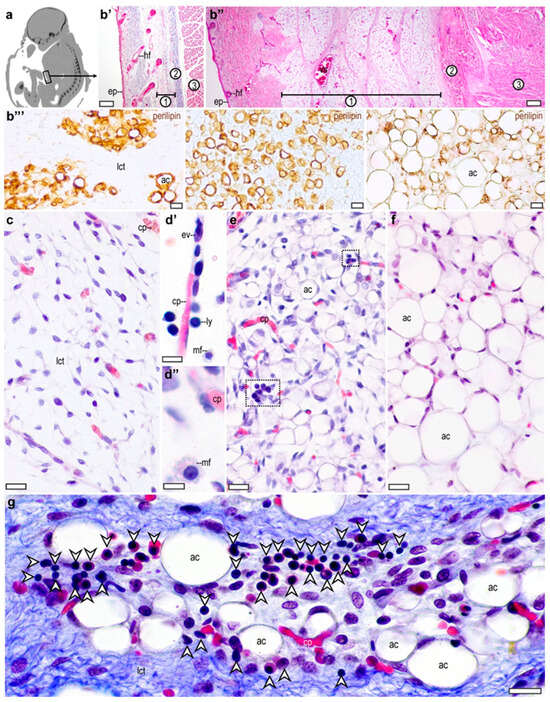

3.1. Adipose Tissue Development in the Human Fetus

3.2. CD45-Expressing Cells in the Developing Adipose Tissue

3.3. Distribution of CD68-Expressing Cells in the Developing Adipose Tissue

3.4. Distribution of CD14-Expressing Cells in the Developing Adipose Tissue